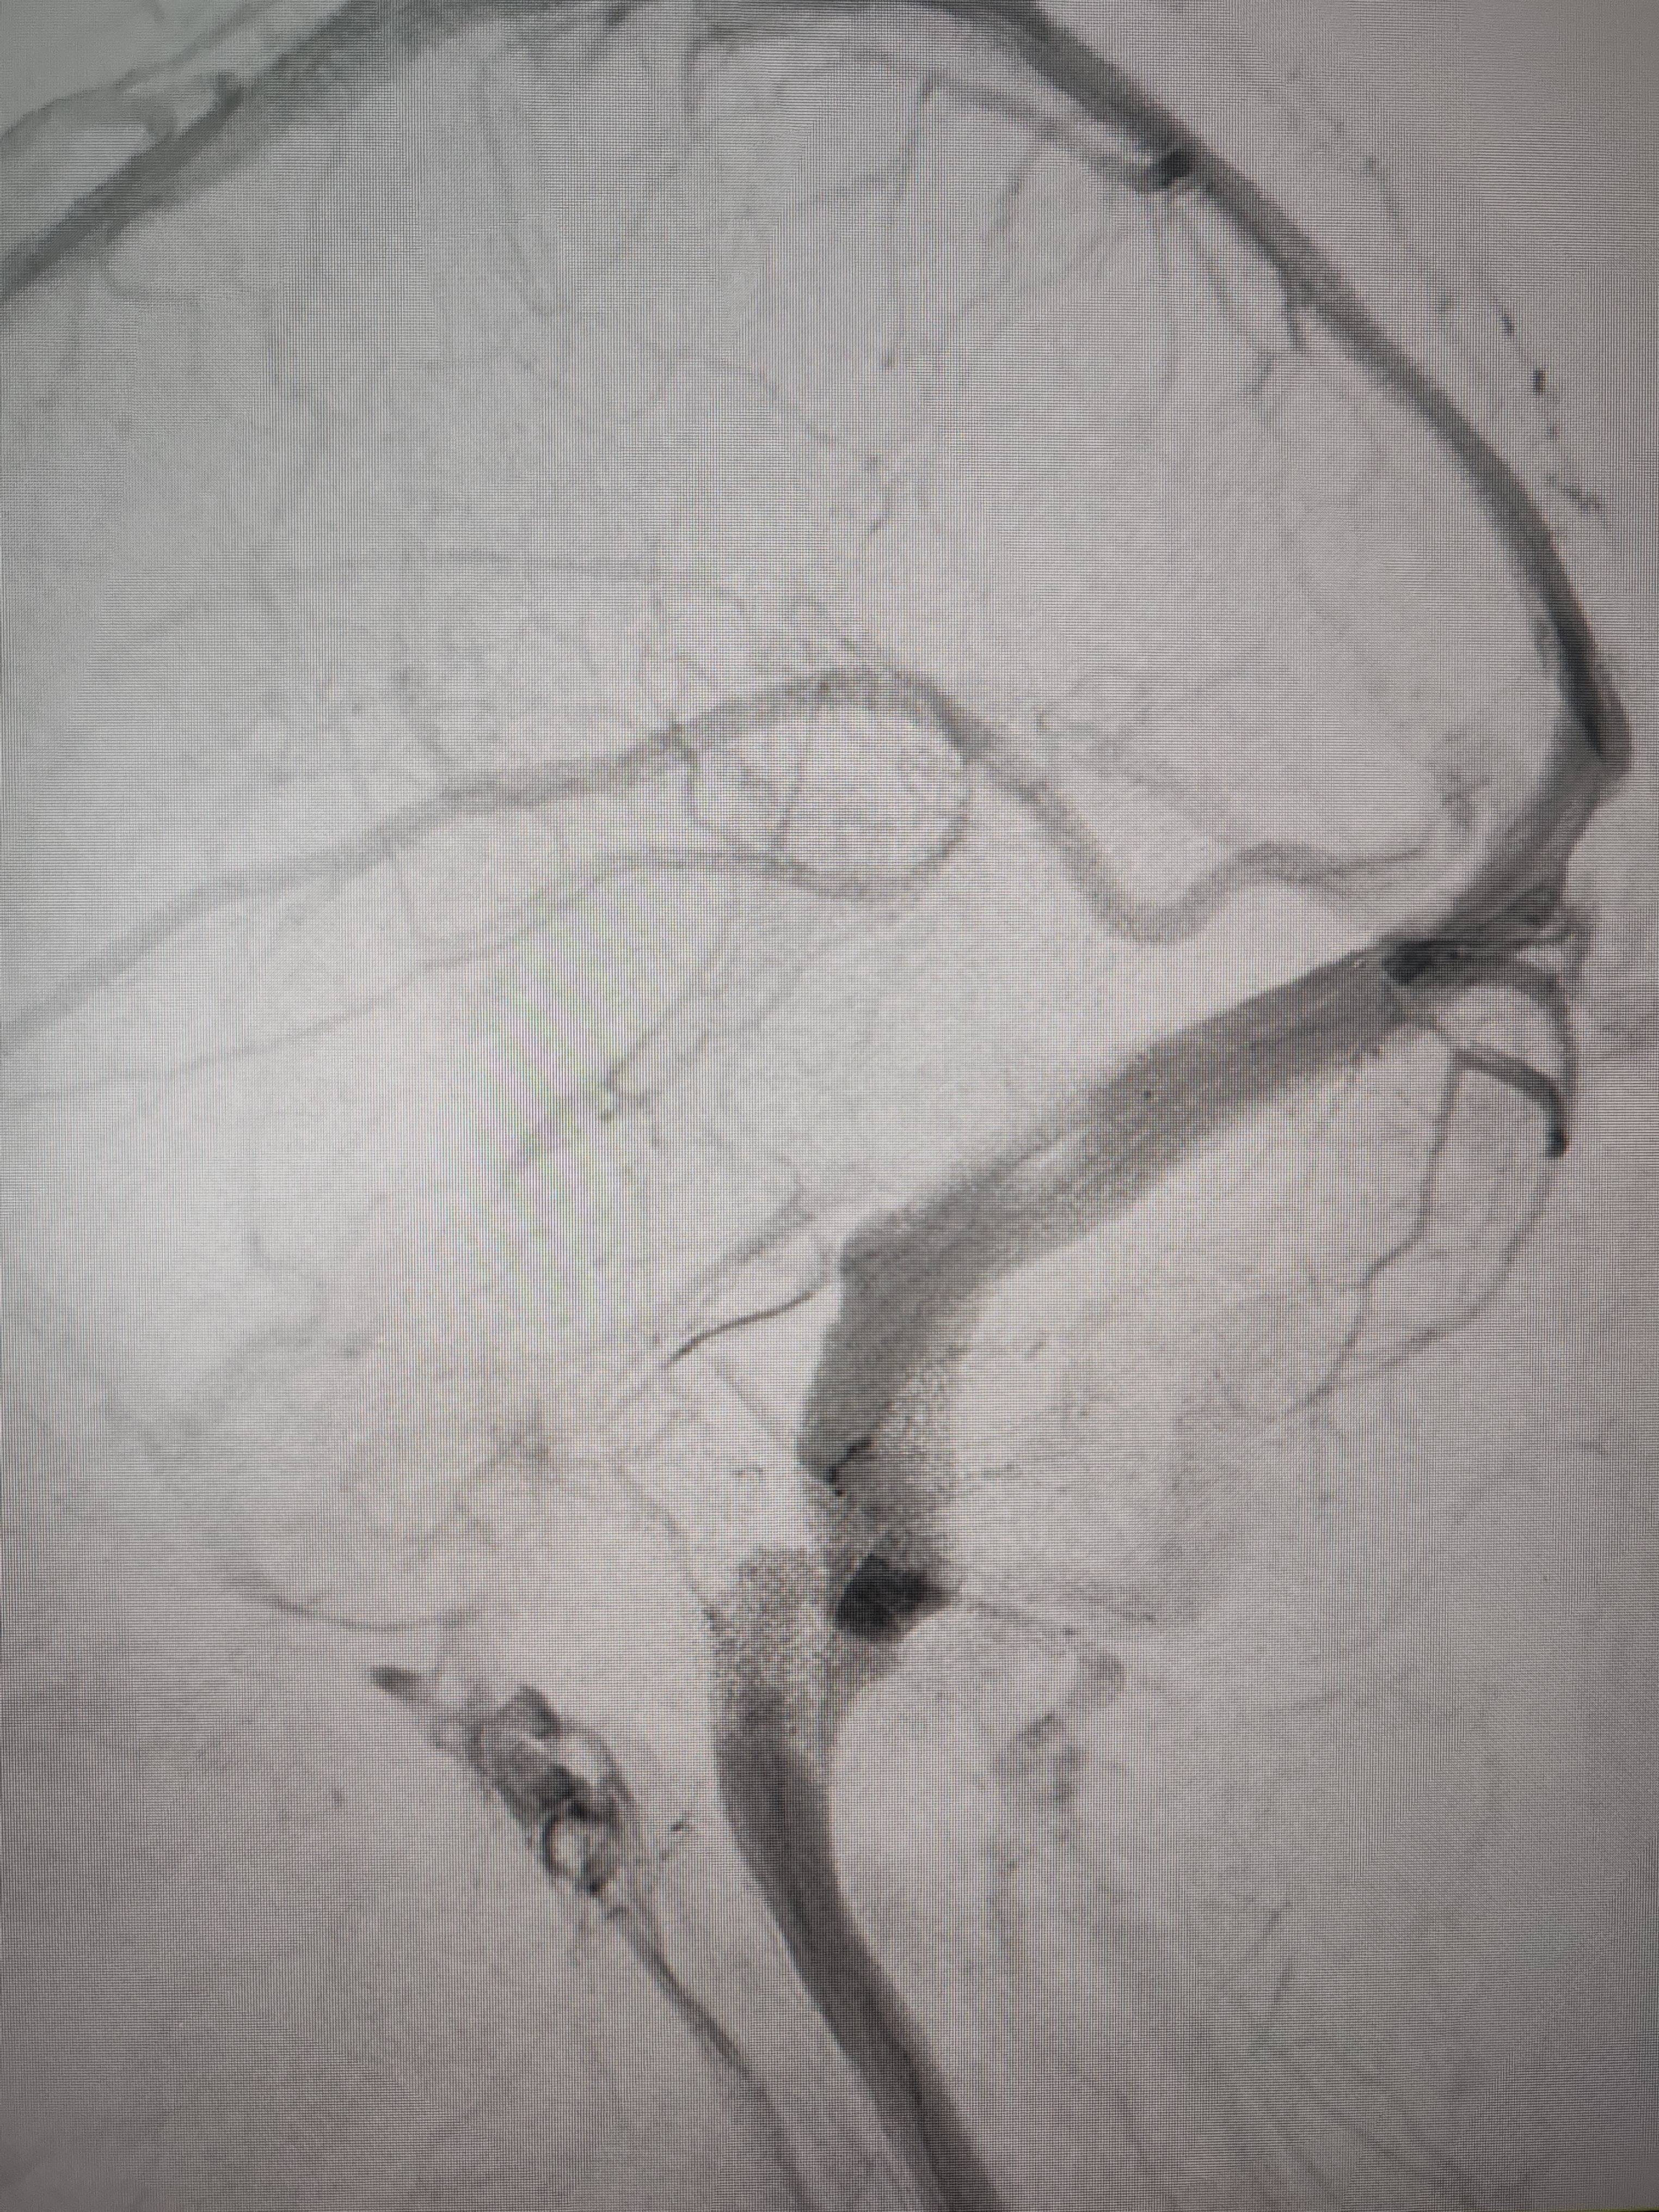

经过静脉窦支架置入手术治疗后,患者的静脉窦“堵点”被打通eth挖矿。 南方+ 欧阳少伟 拍摄

“从手术室出来,麻药清醒以后,我感觉整个世界都清静了,没想到效果这么立竿见影eth挖矿。”减轻病痛的赵女士,术后很是开心,次日就可下床自如活动,目前已康复出院。